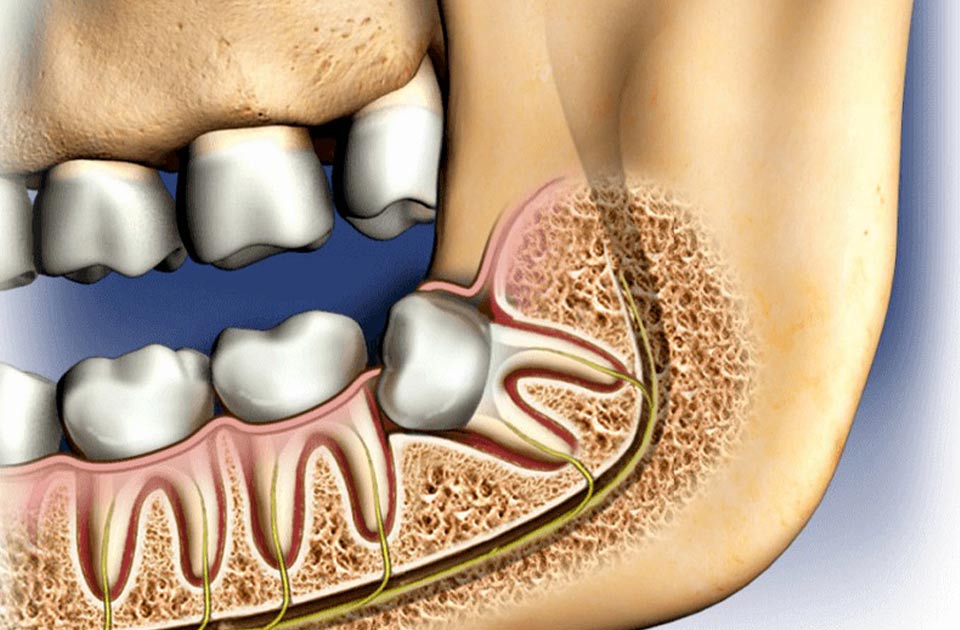

دندان عقل جزو دندان های آخر در دهان می باشد که در سن های 17 تا 25 سالگی به طور کامل خارج می شود افراد معمولا چهار دندان عقل را دارند که دو دندان در فک بالا و دو دندان عقل در فک پایین دهان وجود دارد ممکن است گاهی این دندان ها به طور کاملب رشد نکنند و در لثه باقی بمانند که در این حالت می گویند دندان عقل شما نهفته است .

نهفتگی مزیال : در این رویش ، دندان عقل اگر تاج دندان به عقل به سمت جلوی دهان زاویه پیدا کند به آن دندان نهفته مزیال می گویند .

نهفتگی دیستال : در این رویش دندان عقل ، در صورتی که تاج دندان شما به سمت پشت دهان شما زاویه داشته باشد نهفتگی دیستال در دندان شما رخ داده است که معمولا این مورد در بین افراد رایج تر است .

نهفتگی عمودی : اگر دندان عقل شما در جای درست شروع به رشد کرده باشد اما از خط لثه بیرون نزند نهفتگی عمودی رخ داده است